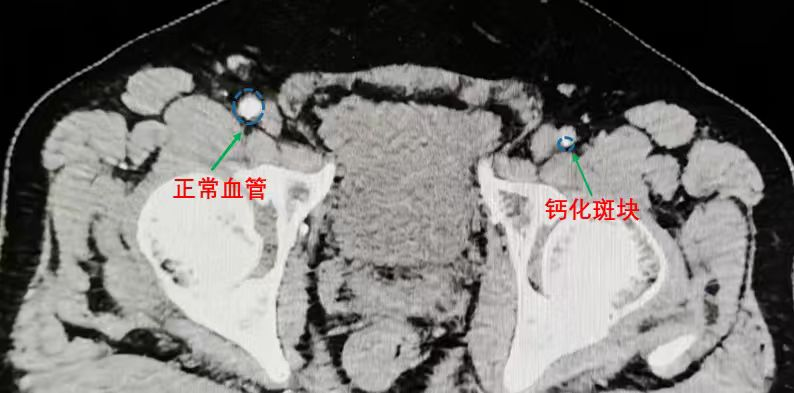

CT横断面显示,患者左侧股动脉管腔不仅闭塞,更严重的是血管壁上长满了“水垢”一样的钙化斑块,管腔被挤压得几乎消失。

“患者这次复发,不仅仅是血栓的问题,更核心的是血管壁的严重硬化和钙化,”中医外科外聘专家罗宇东教授分析道,“对于这种走路只能走30m的重度缺血,必须尽快打通血管。但他的血管像生锈的水管壁上结了厚厚的水垢,非常坚硬。如果强行用球囊去撑,很容易回缩;如果直接放支架,支架无法贴合凹凸不平的钙化壁,远期效果很难保证,且病变位于跨关节部位,再次闭塞机率极高。”